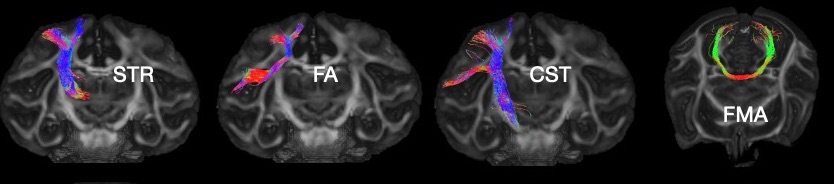

The Figure shows four example tracts generated from the hybrid tractography at 0.6mm including the superior thalamic radiation (STR), frontal aslant (FA), corticospinal tract (CST) and forceps major (FMA).